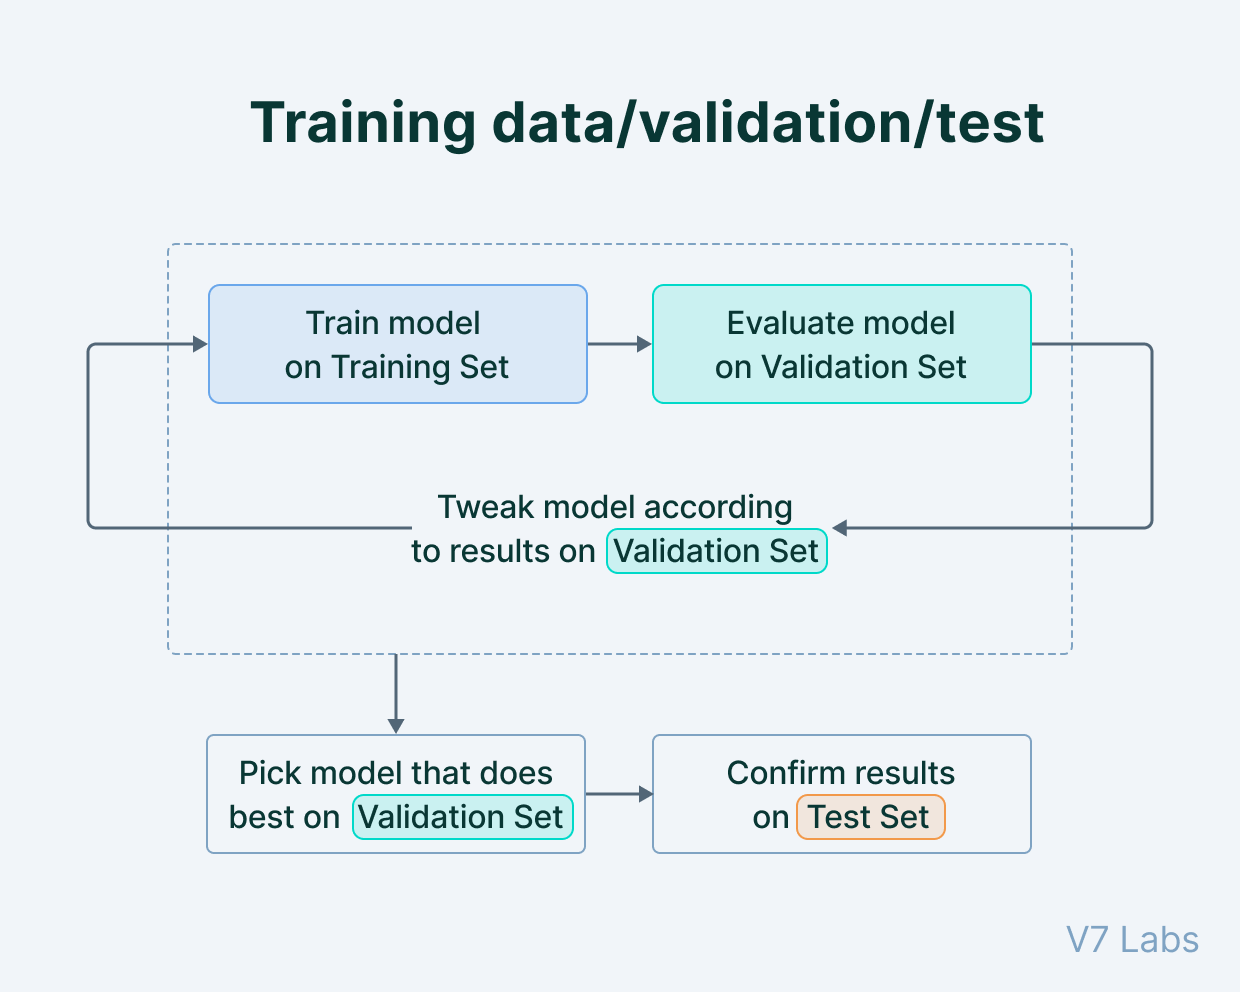

数据集类型

您的数据集需要在部署模型的环境方面具有代表性——这将确保模型的准确性。

使用来自多个不同数据集(例如,不同的成像机器、不同的人群和医疗中心)的图像是降低偏倚风险的理想选择。最常见的是,训练、验证和测试数据的比例接近 80:10:10。

训练、验证、测试数据。

收集数据并训练模型后,是时候使用验证集来检查过拟合或欠拟合,并相应地调整参数。

最后,根据测试集评估模型的性能。

获取质量测试数据集至关重要,因为它可以作为参考标准,并将决定您的训练模型的进一步监管批准。